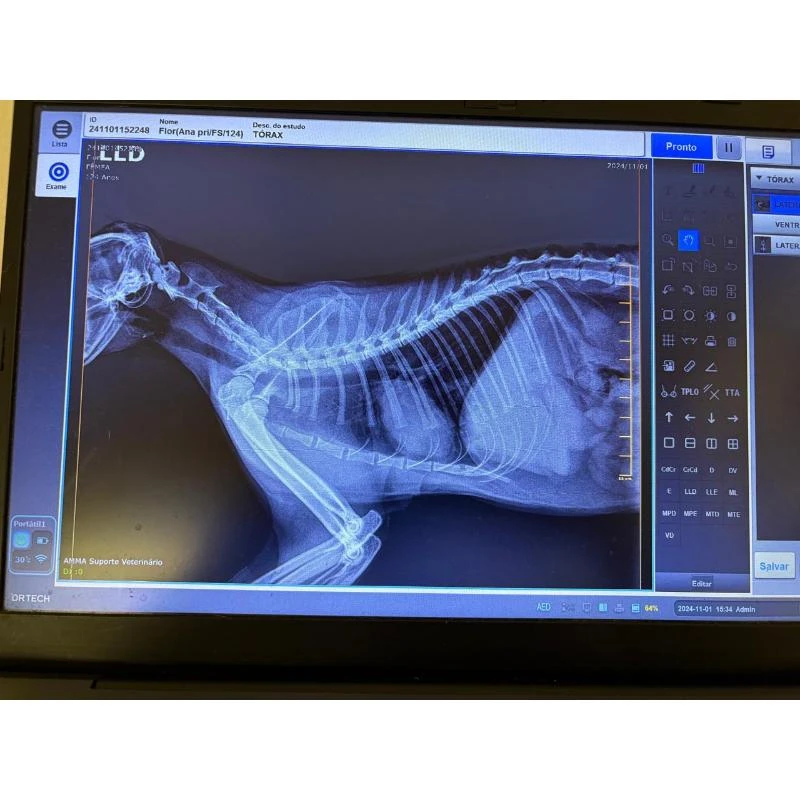

Raio x para cães

raio x para cães: diagnóstico rápido e preciso

O raio x para cães é um procedimento fundamental para o diagnóstico de diversas condições de saúde em animais de estimação.

Com o avanço da medicina veterinária, os serviços de radiografia de emergência estão cada vez mais acessíveis, permitindo um atendimento rápido e eficaz em situações críticas.

Importância do raio x em plantão para cães e gatos

O serviço de radiografia de emergência disponível para animais, como cães e gatos, é essencial para o diagnóstico imediato de fraturas, luxações e alterações internas.

Benefícios do raio x veterinário para cães

O raio x veterinário é um procedimento fundamental para o diagnóstico preciso de diversas condições de saúde em cães e gatos.